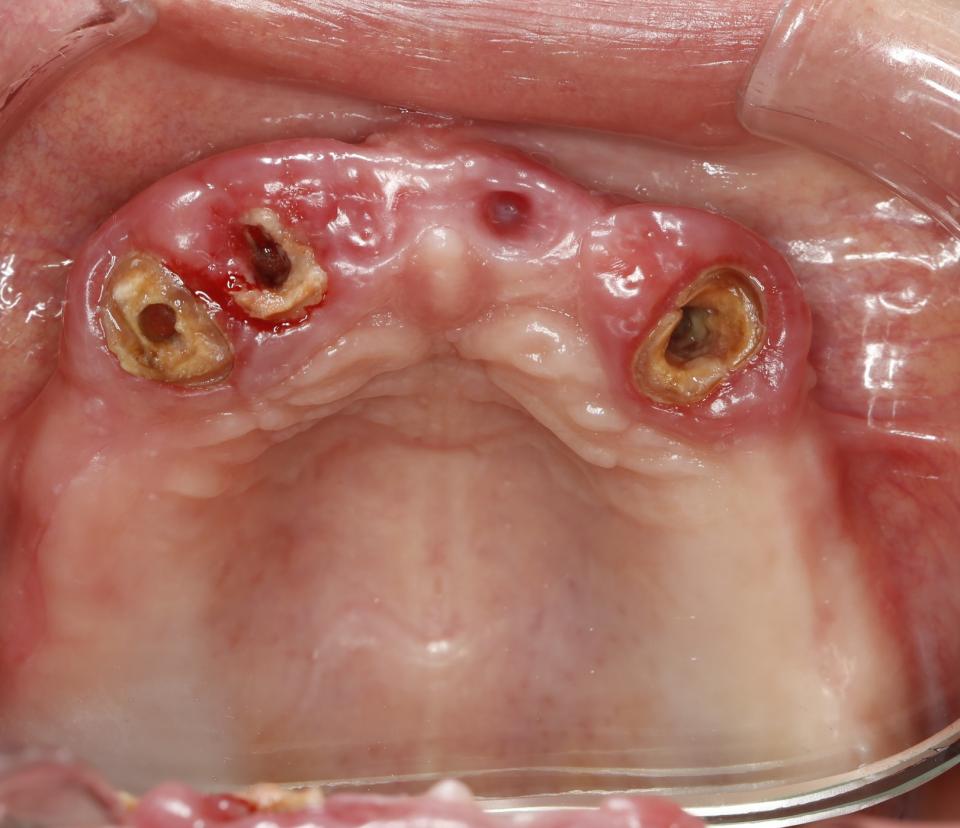

paraschyk1 Опубліковано: 6 червня 2018 Автор Опубліковано: 6 червня 2018 Вот фото зубов где коронки были сделаны пять лет назад с прайсом вдвое дороже чем у меня сейчас. Зубы после такого- трупы.А все от ненадлежащего качества работы и пох.зма в отношении в людям.

paraschyk1 Опубліковано: 6 червня 2018 Автор Опубліковано: 6 червня 2018 Вот фото где также коронки простояли четыре года и пац только выплатил кредит по ним,а спустя два мес. пришлось все убрать и переделывать,ессно за новые тугрики.